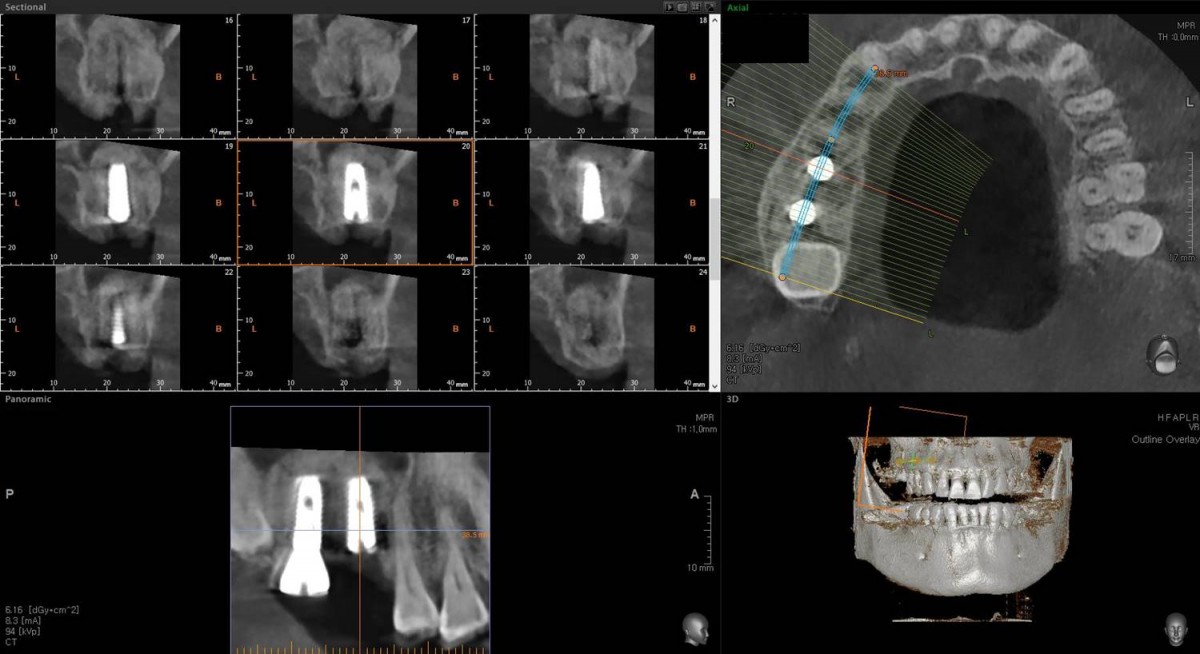

Maxillary Sinus Graft, 2 Implants, Crown Contouring

<GCaks> A 56-year-old male patient had pain-inducing caries, and perio-involved tooth mobility resulted in a tooth fracture at 1st molar. And it was removed months ago. He was a heavy smoker and showed poor oral hygiene.